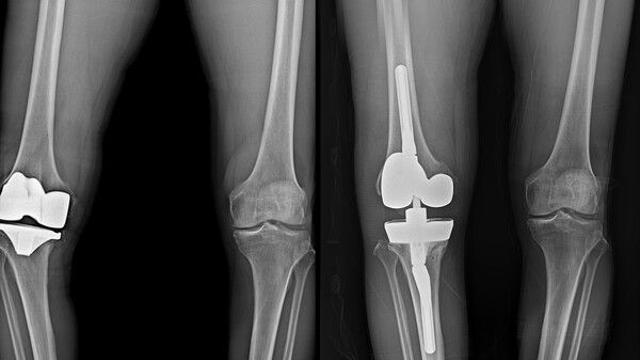

- 연세사랑병원, 고난도 인공관절 재치환술 전문성 강화

- 2026.01.28 [포인트경제]